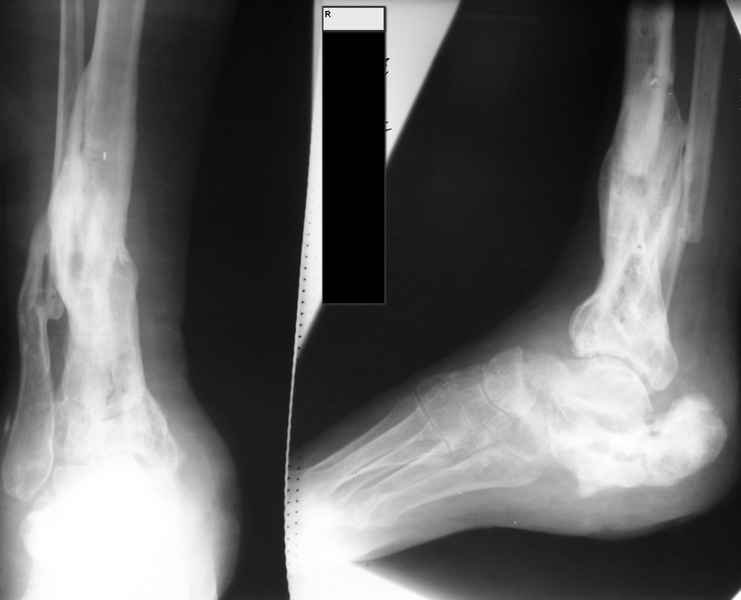

Молодая девушка со сросшимися многооскольчатыми переломами пяток и голеней.Young girl

with fractures of the calcaneus

Больная Н., 25 лет, падение с высоты (2008 г.). Жалобы на боли в области голеностопных

суставах, в области пяток при ходьбе. Лечилась в аппаратах внешней фиксации по поводу

открытых оскольчатых переломов обеих голеней, переломов пяток. Далее по поводу

несросшихся переломов голеней ЧКОС аппаратами внешней фиксации. Переломы срослись,

аппараты демонтированы весной 2010г. В левой пяточной области в месте проведения спицы

имеется сукровичное отделяемое. При ревизии гноя нет. Чем помочь девушке?

Patient N., age

25, falls from heights (2008). Complaints of pain in the ankles, in the heel when walking. She

was treated by external fixation on open comminuted fractures of both legs, fractures of the

calcaneus. Then she was treated by external fixation from nonunion of both legs. Now

fractures are fused, apparatuses removed in the spring of 2010. How to help a girl?